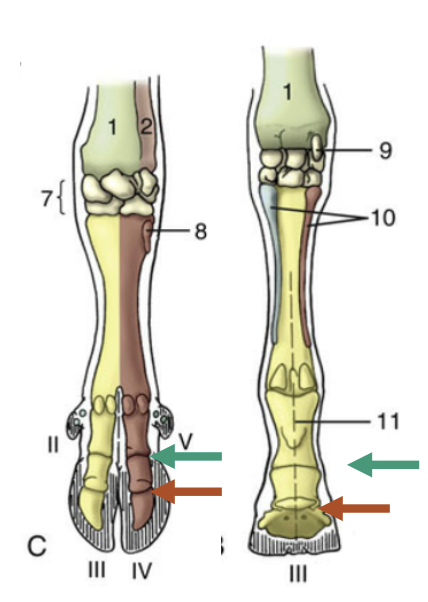

Green arrow?

Proximal interphalangeal joint

Red arrow?

Distal interphalangeal Joint

Which joint it shown?

Metacarpophalangeal Joint